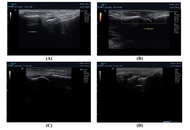

To evaluate the relationship between serum calprotectin and serum amyloid A with musculoskeletal ultrasonographic findings in rheumatoid arthritis (RA) patients, as RA is the most common chronic inflammatory joint disease in which the infiltration and activation of inflammatory cells are important. Calprotectin and serum amyloid A protein are over-secreted in response to acute and chronic inflammation. Musculoskeletal ultrasound is more sensitive than physical examination for the evaluation of synovitis.

A control group of 30 healthy individuals, 30 patients with active RA, and 30 patients with inactive RA participated in this cross-sectional study. Utilizing the RA disease activity (Disease Activity Score 28, DAS28) score was evaluated. Serum amyloid A and serum calprotectin were measured in all participants, and musculoskeletal ultrasound on the hands and wrists were done for all subjects.

A significant difference was observed among the studied groups with respect to serum calprotectin and serum amyloid A levels (P < 0.001). A significant positive correlation was observed between serum amyloid A and several inflammatory and clinical parameters, including C-reactive protein (CRP), erythrocyte sedimentation rate (ESR), DAS28 score, serum calprotectin, and synovitis. Similarly, serum calprotectin levels demonstrated a significant positive correlation with ESR, DAS28 score, serum amyloid A, and synovitis. These findings highlight the potential value of both serum amyloid A and serum calprotectin as biomarkers reflecting disease activity and inflammatory burden in RA.

Serum amyloid A and serum calprotectin can be used as markers of RA activity.